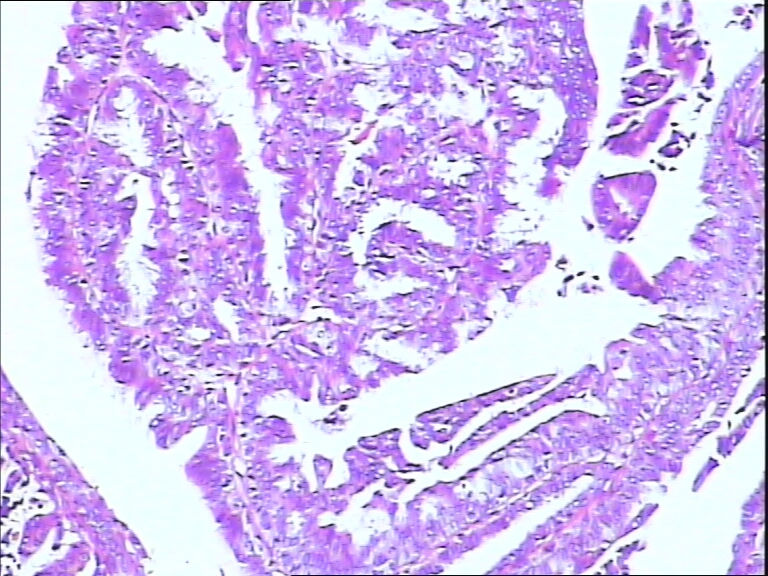

B3785左乳头包块!

42y

左乳头有3mm结节

灰白不整形组织一块:0.7*0.5*0.4

• 左乳头包块!图4

图4

标签:导管内乳头状肿瘤

导管内乳头状瘤,导管上皮不典型增生。

乳头腺瘤(nipple duct adenoma)或称乳头的乳头状瘤

导管内乳头状瘤,局灶伴不典型增生。

导管内乳头状结构,细胞无异型性,诊断导管内乳头状瘤。